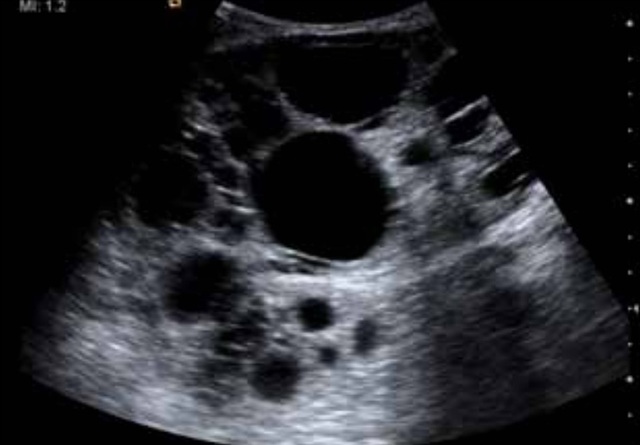

其中一名肾脏移植接受者是一名 24 岁男性坏死性肾小球肾炎终末期患者,其 10 年前曾做过肾移植手术。在移植术后的肾脏超声检查中发现,移植肾发现有两个类圆形囊肿,直径分别为 2.0cm 和 1.0cm。数年后肾脏 B 超检查结果如下。